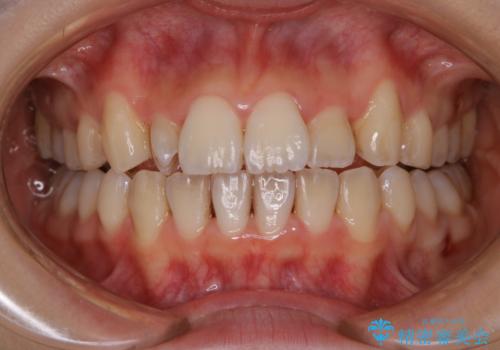

- インビザラインでの矯正治療中の方です。全体的に黄ばみ・黒ずみが気になるとのことでした。

PMTC60分コースを行いました。

PMTC(保険外治療)は、毎日の歯磨きで落としきれない汚れや、コーヒ、紅茶・タバコのヤニなどの着色も除去します。目には見えない歯と歯の間・歯肉の境目・インビザライン中はアタッチメント周囲などに残っているプラーク(歯垢)もしっかり取り除きます。PMTCでは専門的な機械や材料を使用して、徹底的に汚れを除去するため、虫歯・歯周病・口臭予防などにつながります。

またPMTCを行うことで、ご自身本来の歯の色になり自然な明るさになります。